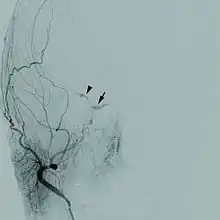

Cerebral angiogram of a carotid-cavernous fistula